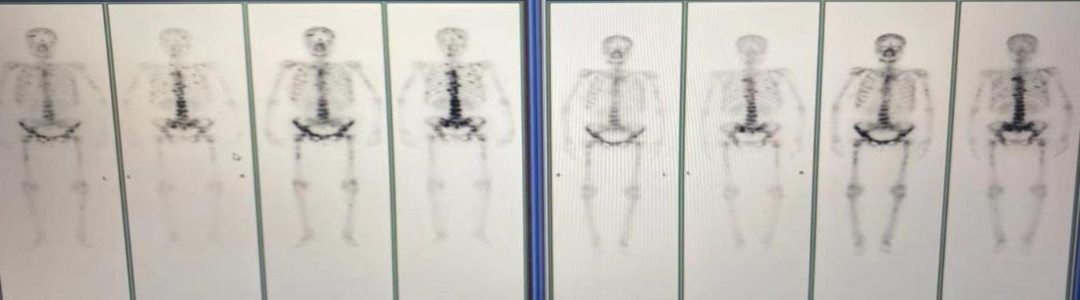

图3.骨扫描

2021年4月7日骨扫描:全身多发骨质代谢异常,考虑多发骨转移。